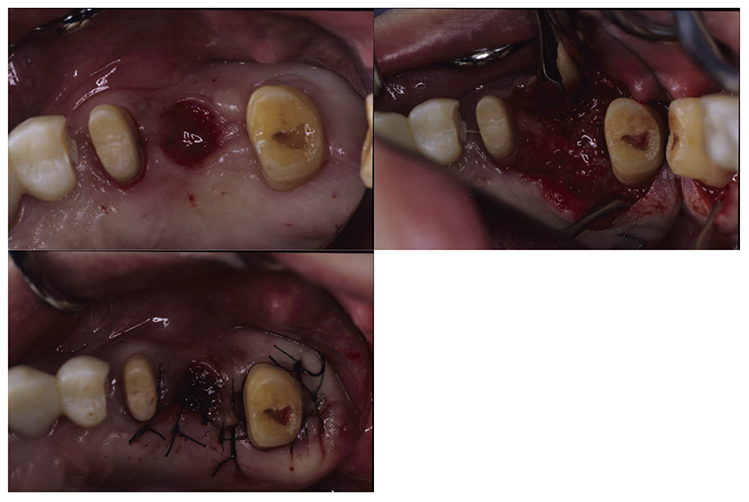

At the reevaluation examination after completion of basic periodontal treatment, deep periodontal pockets and grade 2 furcation involvement were observed. Therefore, in April 2010 (age 42), enamel matrix proteins were applied in a procedure for periodontal regeneration (Fig.4),and in June of the same year, gingival flap operation and distal wedge procedure were performed on 27 (Fig.5). For the remaining PD on the lingual side of 36 and 46, due to insufficient keratinized gingiva, the option was to stabilize the condition with SRP.

Fig 4

(Fig.4) Enamel matrix proteins were applied in a procedure for periodontal regeneration in the maxillary left molar (April 1, 2020)

Fig 5

(Fig.5) Gingival flap operation and distal wedge procedure were performed on the maxillary left second molar (June 2010)